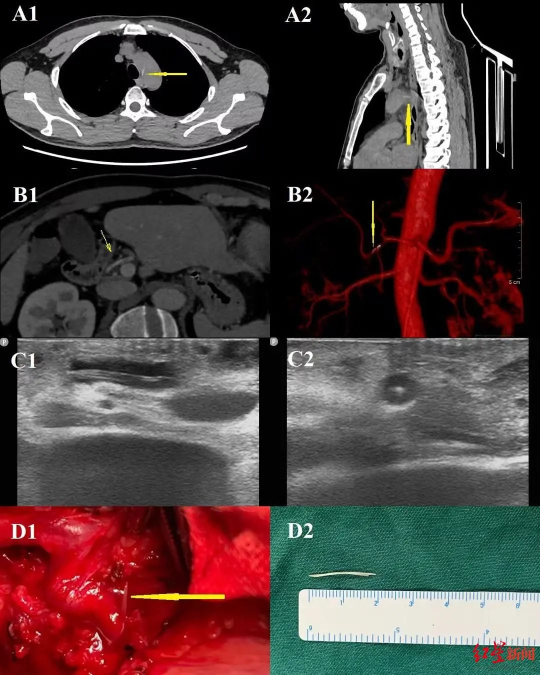

▲检查结果提示鱼刺的具体位置

本例患者鱼刺刺入主动脉形成主动脉食管瘘,但未出现纵隔感染、主动脉大出血等严重并发症。虽然急诊手术未找到鱼刺,但修补了主动脉破口,同时使用聚维酮碘冲洗胸腔,预防了严重胸腔及纵隔感染发生。转院后在放射科和超声科帮助下,通过图像后处理及三维重建技术准确定位鱼刺位于肝动脉中,为后续制定手术方案给予了极大帮助。